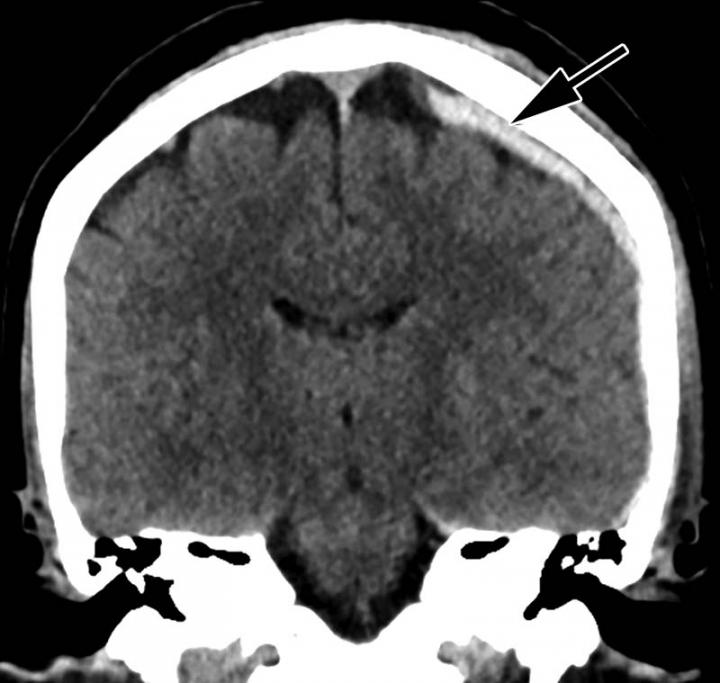

"Radiology has made substantial contributions to the detection of non-accidental trauma in children, and identification of pediatric violence is an essential component of a radiologist's training, but little is known about the role of imaging in the detection of intimate partner violence," said Bharti Khurana, M.D., the study's principal investigator, a radiologist at Brigham and Women's Hospital and assistant professor of radiology at Harvard Medical School in Boston. "Medical images can offer early clues of IPV based on location and pattern of both new and old injuries."

The researchers found that almost all of the intimate partner violence victims were women (96 percent). Victims had a mean age of 34.2 years. Thirty-seven percent were African-American and 28 percent were Hispanic. Victims of intimate partner violence, on average, underwent approximately four times more imaging exams in the preceding five years compared to the control group. Acute fractures and obstetric/gynecologic findings, such as pregnancy loss and intrauterine growth restriction, were associated with two to four times higher odds of domestic violence.